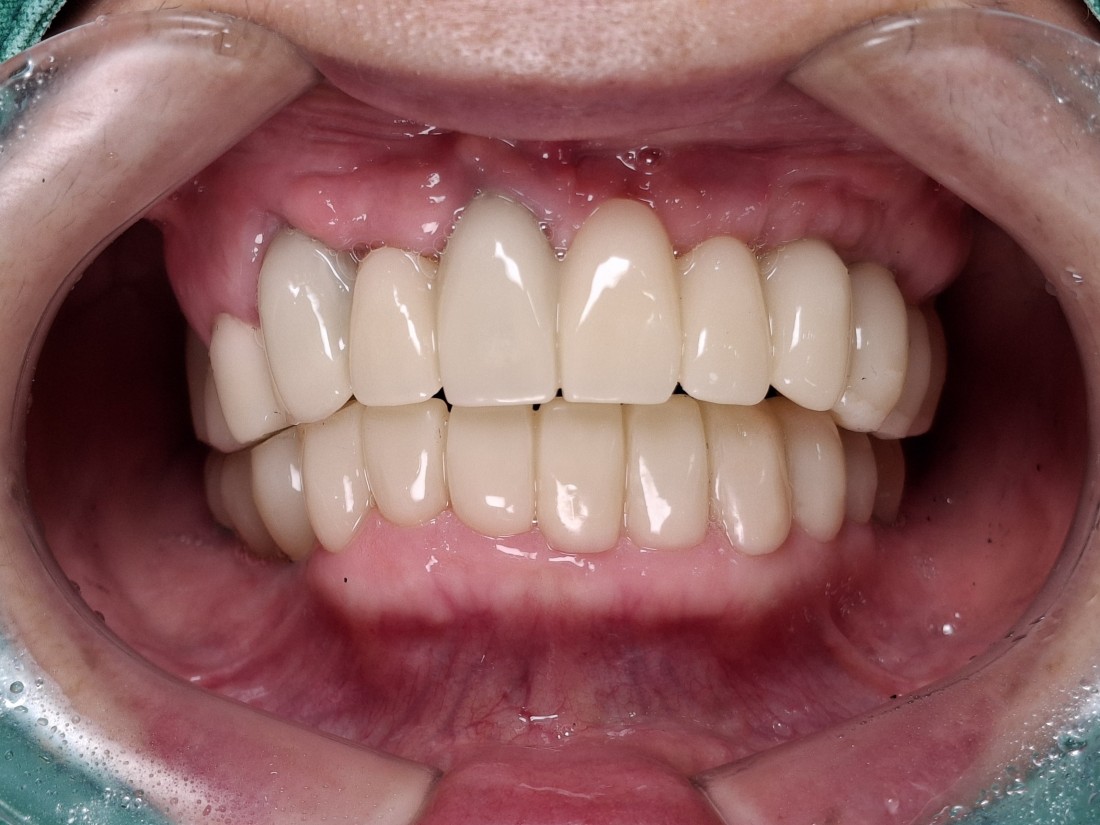

광주 상악임플란트를 해야하는 때가 오면

무엇보다도 '예쁘고 잘 씹어지게'

임플란트 진료를 받고싶으실텐데요.

광주 상악임플란트 치과는

4층 자체 치아기공소를 운영하고 있으며

보철물 디자인 퀄리티를

굉장히 중요하게 생각하고 진료하기 때문에

자연치아만큼 예쁘면서도

잘 씹어지는 광주 상악임플란트 진료를

보장할 수 있습니다.

만약 불편한 점이 생기셔도

자체 치아기공소에 바로 수정이 가능하여

빠르고 예쁘게, 잘 씹어지는

광주 상악임플란트를

완성하고 있습니다.